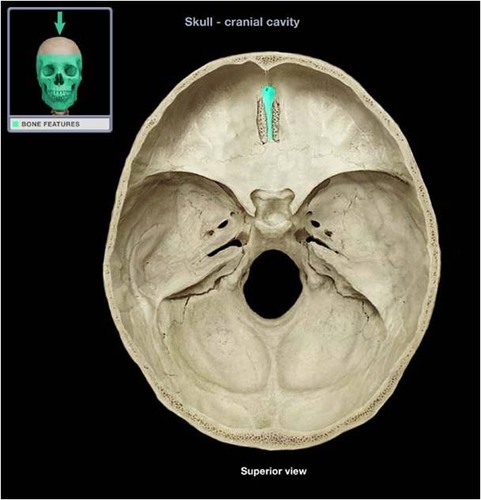

crista galli

cribriform plate